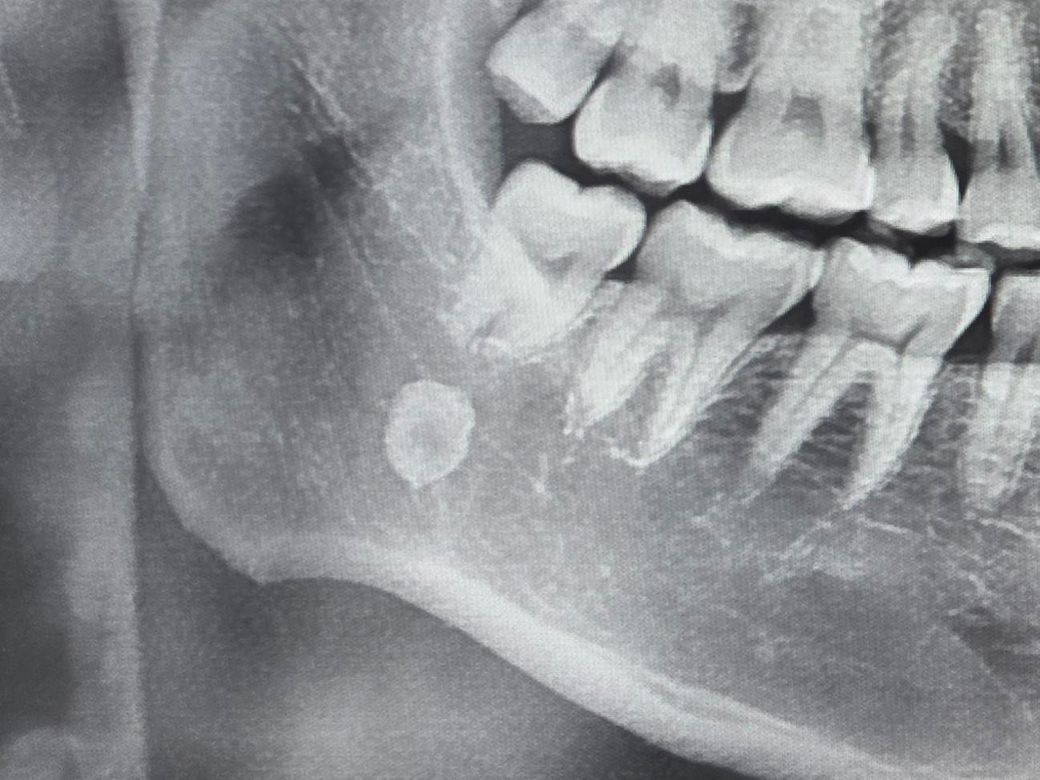

첨부한 엑스레이 사진을 보면 턱쪽에 뼈나 치아

첨부한 엑스레이 사진을 보면 턱쪽에 뼈같은것이 관찰되는데 무엇인가요

저런경우도 있는지 무엇때문인지 왜그런건지 궁금합니다

idiopathic sclerosis 로 보여지며 특별히 치아와 연관되어 있다기보단 말 그대로 원인은 모르나 골이 경화된 상태입니다. 크게 문제는 없을 확률이 높습니다.

대부분 이러한 사진에서 보이는 것은 골경화증일 가능성이 크며 단순히 뼈의 밀도가 부분적으로 높아 나타나고 있을 수 있습니다. 골경화증은 정상적인 상황이므로 크게 문제가 되지 않으나 해당 위치는 타액선과도 연관되어 있어 타석 등일 가능성도 있습니다. 따라서 정확한 판단을 위해서는 x-ray 뿐만 아니라 biopsy 등을 해야할 수도 있어 보입니다.